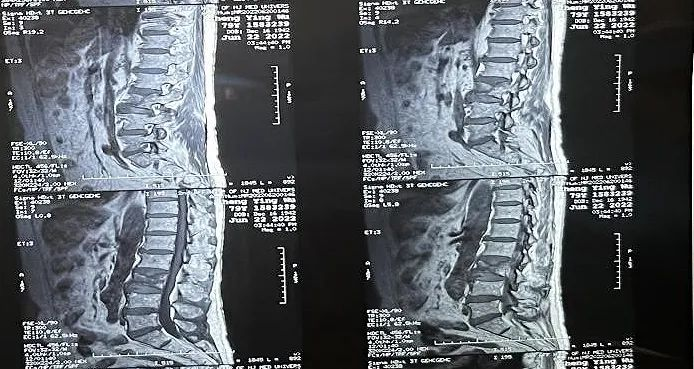

临床手术过程

术中切口5毫米,在大平板C臂机的透视指引下,确定了进针的方向及进针的深度。经椎弓根向椎体置管,建立通道,插入骨扩张器(球囊)。球囊扩张恢复椎体高度,并在椎体内形成空腔,确定骨水泥的注入剂量,并注入骨水泥观察其扩散情况。

大平板C臂机临床图像